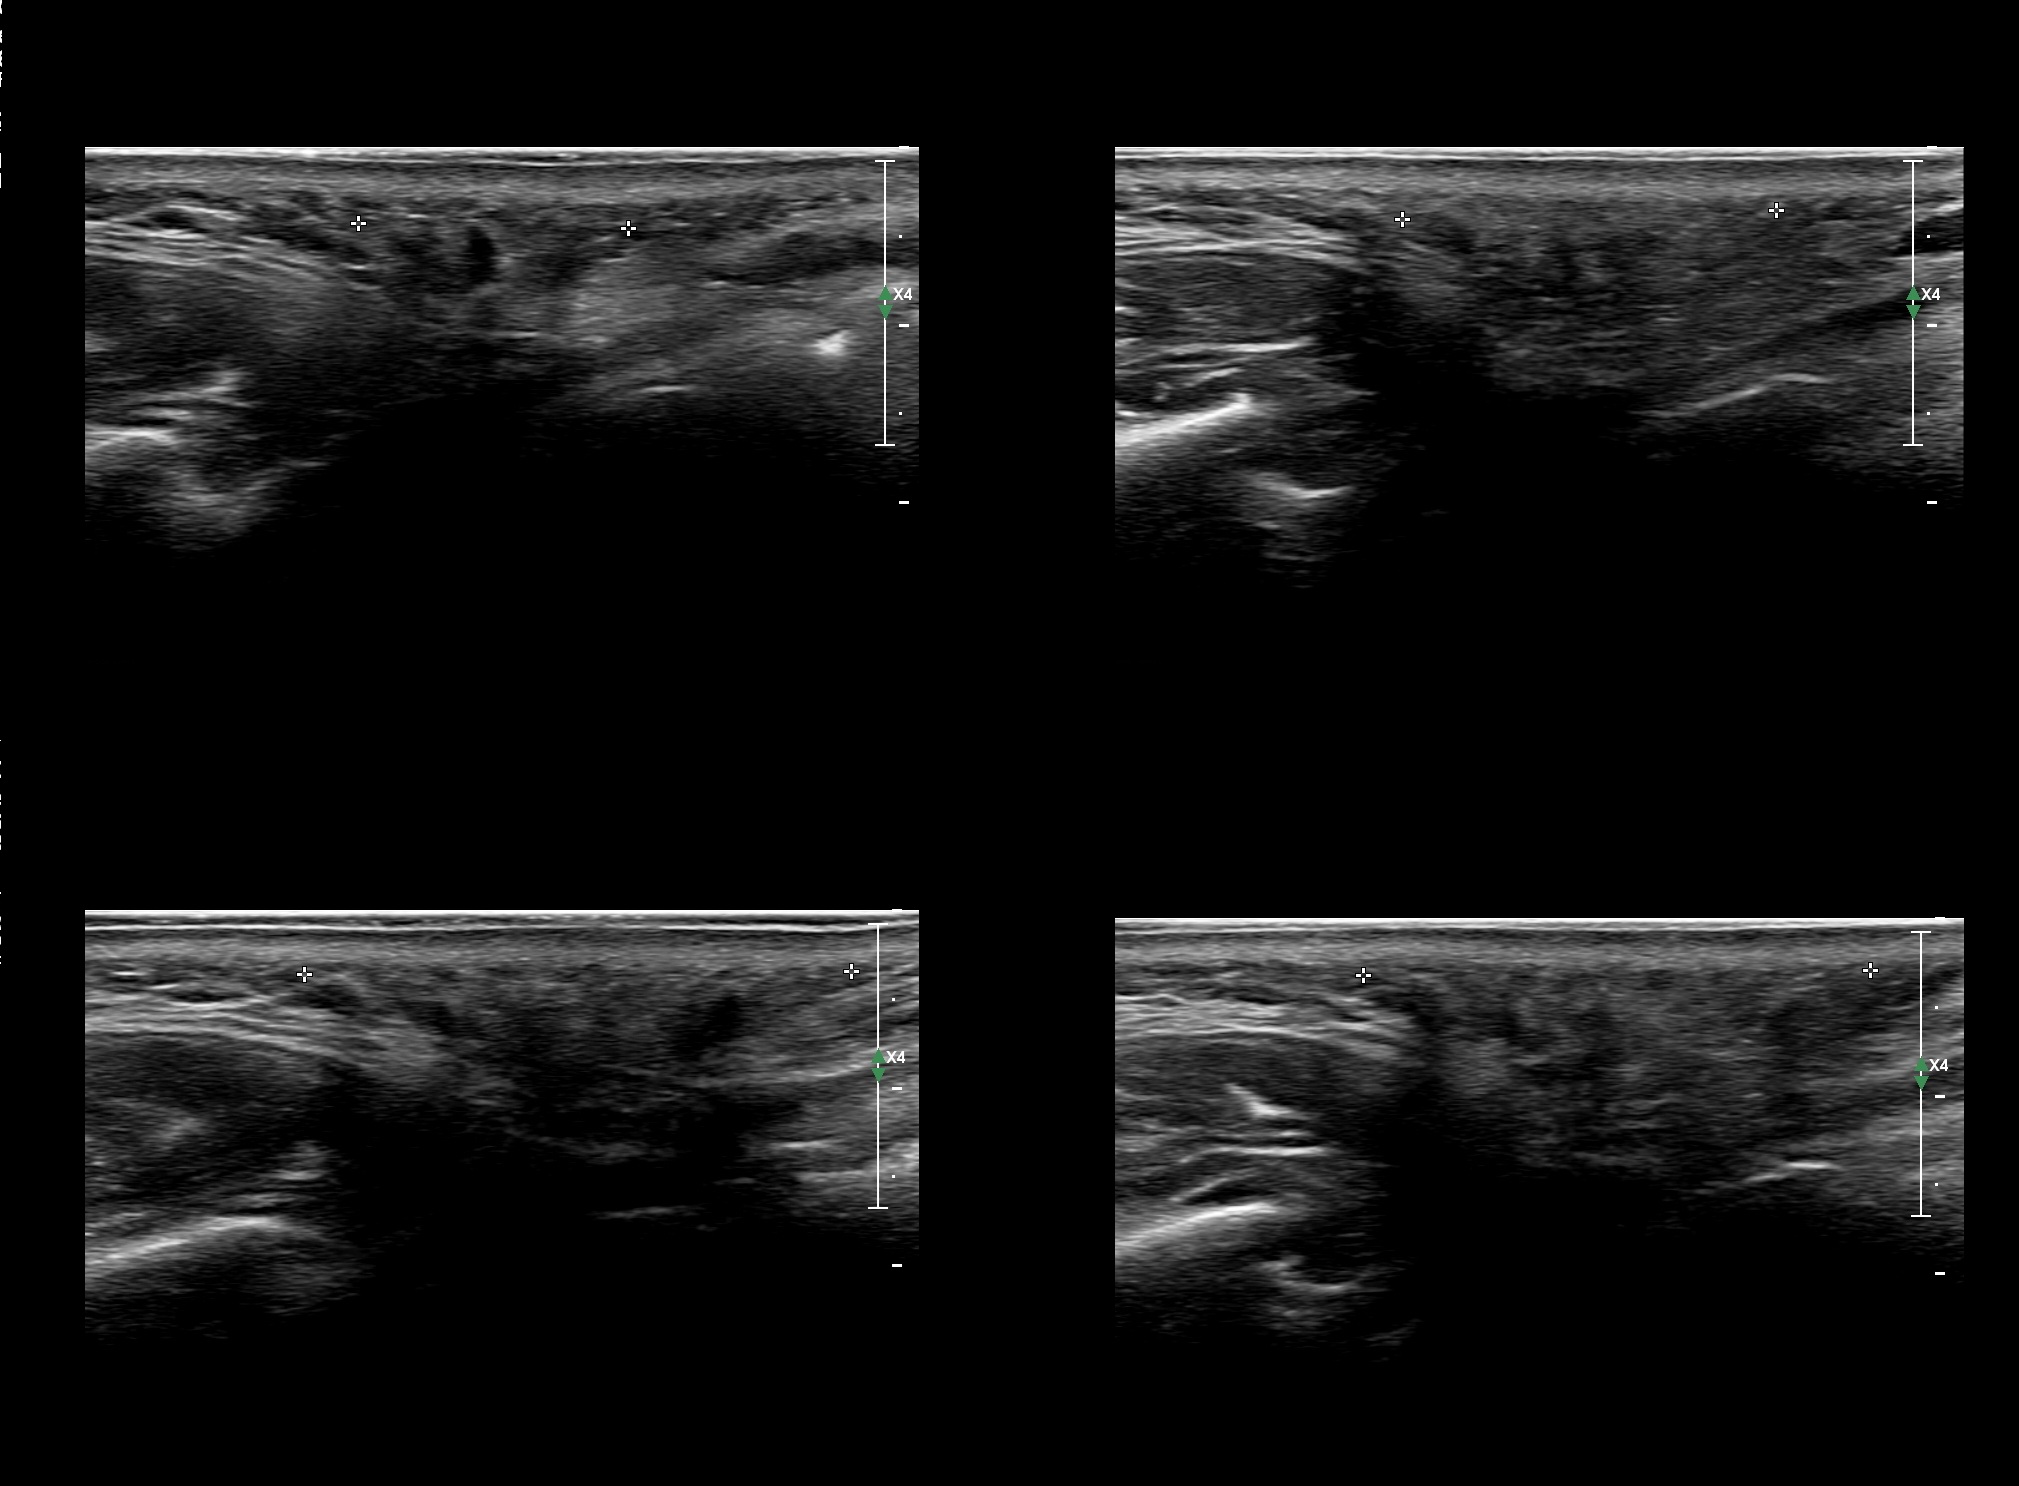

Fillers

Draw in the second image below where the fillers are located. To check if your answer is correct, swipe the first image to the right.